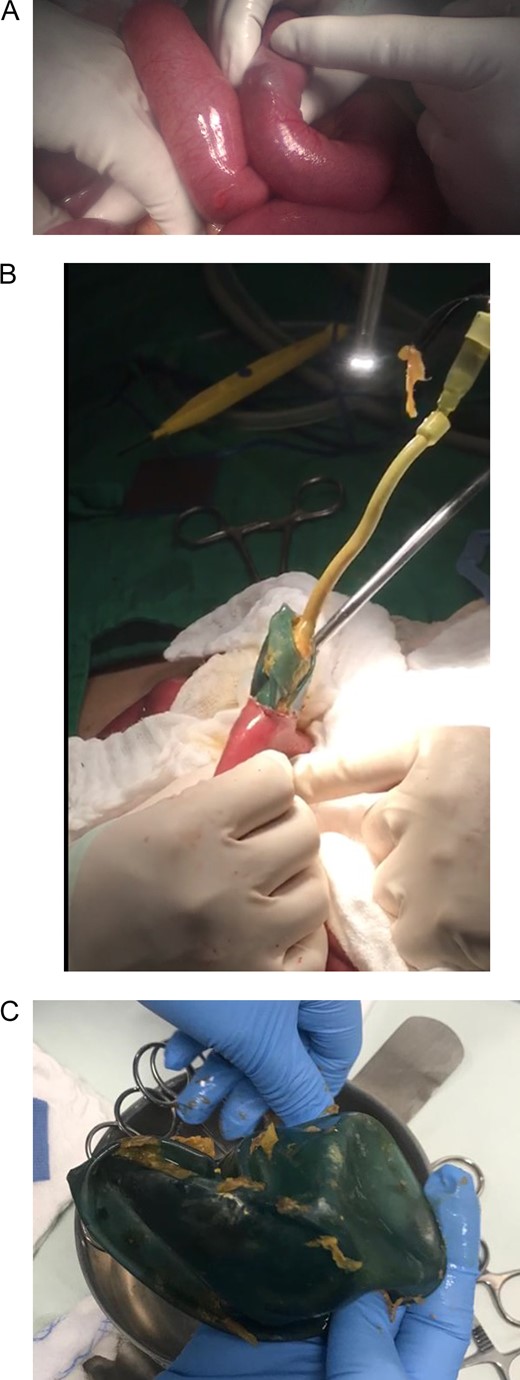

Bowel obstruction due to the migration of the deflated intragastric balloon was suspected. Following a laparoscopic approach, the intestinal loops were dilated, and 100 ml of inflammatory fluid were noticed in the abdominal cavity. However, the definite site of obstruction could not be accessed (Fig. 2). Due to this, a laparotomy was decided. There was an important dilatation of all the loops of the small bowel, and the bowel walls were thickened but no perforation was detected. Near the ileocecal valve, a clear bulging of the bowel wall caused by the deflated impacted balloon was externally visible. A 3 cm transverse enterotomy was performed and the deflated gastric balloon was gently pulled out. The enterotomy was subsequently closed and the rest of the procedure was completed without complications (Fig. 3).

(A) Laparotomy, showing gastric balloon within the bowel. (B) Removal of the deflated gastric balloon. (C) Deflated gastric balloon.